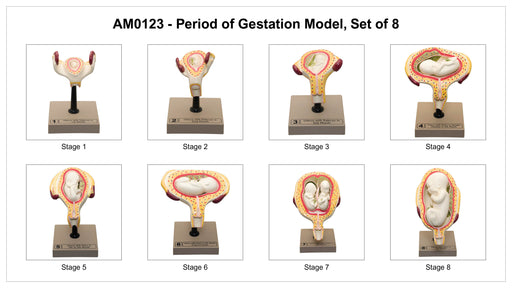

Eisco Pregnancy Series - Embryonic and Fetal Development, Set of 9 Models

Set of nine individual models mounted on stands show the stages of human development. Each model comes with a stand and a rod for display Hand pai...

View full detailsAM0122 -

Human Embryo/Fetus Development in Utero Model Set

The detailed 3D renderings of the development of the human fetus in utero with their vibrantly colored anatomy are ideal for studying the complete ...

View full detailsAM0123 -